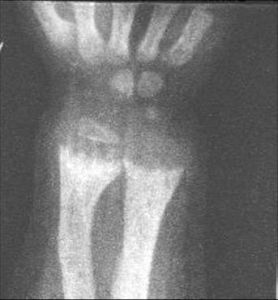

(1)長骨骨骺端X線攝片 發現長骨骨骺端佝僂病的特異X線表現,早期X線長骨骺部鈣化預備線模糊;極期鈣化預備線消失、骨骺端增寬、骺端呈杯狀或毛刷狀改變,骨質稀疏、骨幹彎曲變形或骨折。